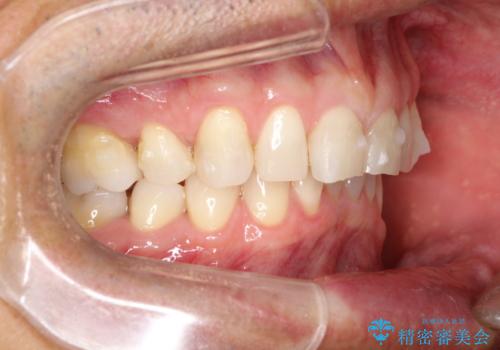

上の前歯の隙間とがたつきをインビザラインできれいな歯並びへ

- 以前矯正治療を他院にて行っており、最近上顎の隙間とガタガタが気になるとのことで来院されました。

上顎のみインビザラインにて矯正治療を行うこととなりました。

使用時間を守っていただけたので、比較的スムーズに矯正を終了することができました。